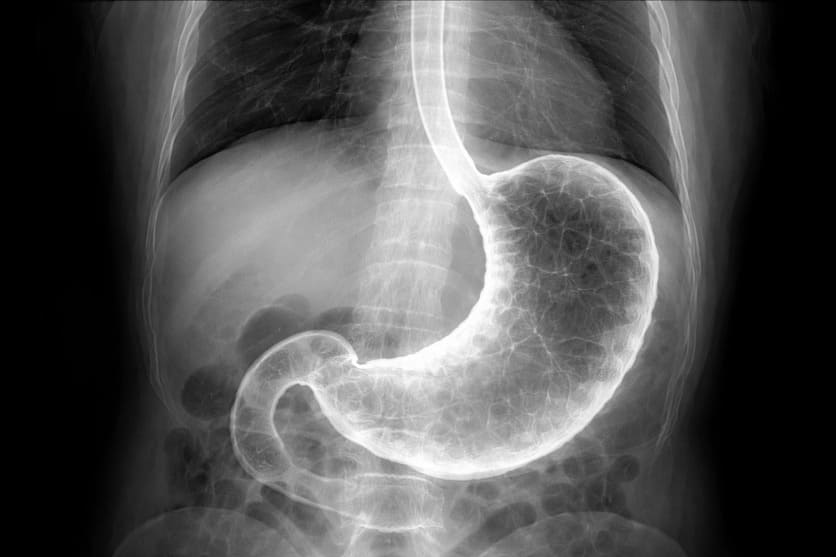

La radiografia allo stomaco è un esame diagnostico radiologico che, nella pratica clinica, valuta non solo lo stomaco, ma anche l’esofago e la prima parte dell’intestino tenue (duodeno).

L’esame utilizza i raggi X associati a un mezzo di contrasto orale, solitamente a base di bario, che permette di visualizzare la forma, il rivestimento interno e in parte la funzionalità del tratto digestivo superiore. Grazie a questa metodica è possibile osservare il passaggio del contrasto attraverso esofago, stomaco e duodeno e individuare eventuali alterazioni anatomiche o funzionali.